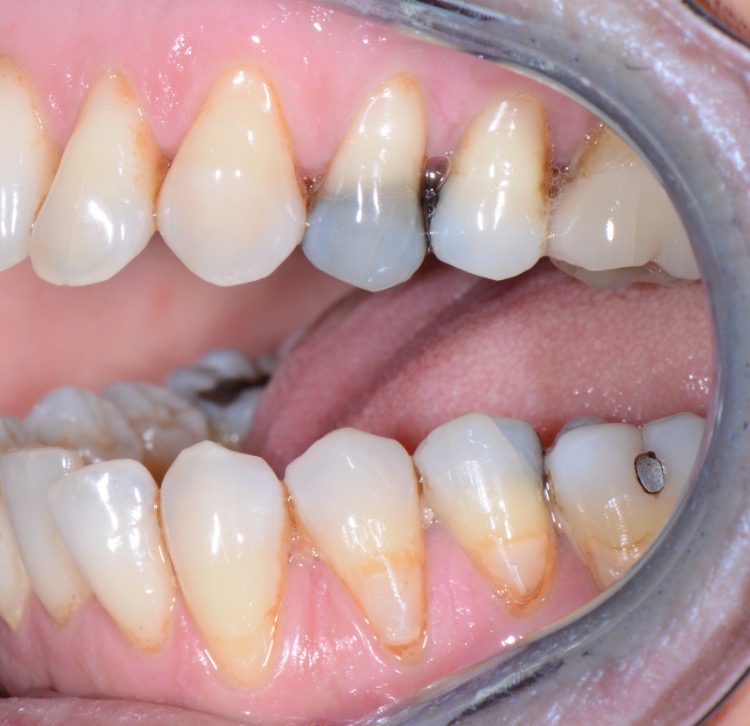

Nos réalisations : Conjointe

Céramique sur Zircone

Translucide, elle reflète la lumière aussi naturellement que l’émail.

Biocompatible elle est garante d’une excellente intégration gingivale.